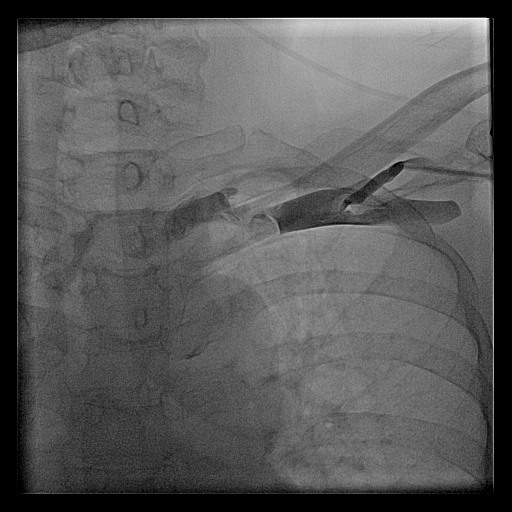

Venogram

• Difficult puncture

• Pre-existing leads

• 10-15 ml of contrast from ipsilateral arm

• Management of stenosis

Puncture with venogram